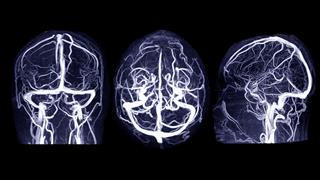

Η διάγνωση ενός ενδοκρανιακού ανευρύσματος, η οποία ανακαλύπτεται ολοένα και περισσότερο τυχαία κατά την απεικόνιση που αφορά άλλες αιτίες, μπορεί να είναι τόσο στρεσογόνος για τους ασθενείς που μπορεί να οδηγήσει ακόμη καισε σε ψυχικές ασθένειες. Σύμφωνα με μελέτη η οπο΄πια δημοσιεύθηκε στο περιοδικό "Stroke", οι νεότεροι ενήλικες είναι εκείνοι που διατρέχουν σημαντικό κίνδυνο.

Οι νευροακτινολόγοι εκτιμούν ότι περίπου ένα έως 2% των ενηλίκων έχουν ένα ή περισσότερα ανευρύσματα στις εγκεφαλικές αρτηρίες. Οι προεξοχές του τοιχώματος του αγγείου τείνουν να σπάνε μόλις φτάσουν σε ένα ορισμένο μέγεθος, με αποτέλεσμα να προκαλείται απειλητική για τη ζωή υπαραχνοειδής αιμορραγία.

Τα μικρότερα ανευρύσματα του εγκεφάλου μπορούν να σκληρυνθούν από το εσωτερικό χρησιμοποιώντας έναν καθετήρα με σπείραμα, ενώ τα μεγαλύτερα ανευρύσματα απαιτούν χειρουργική επέμβαση κατά την οποία ένα κλιπ διαχωρίζει το ανεύρυσμα από την αρτηρία.